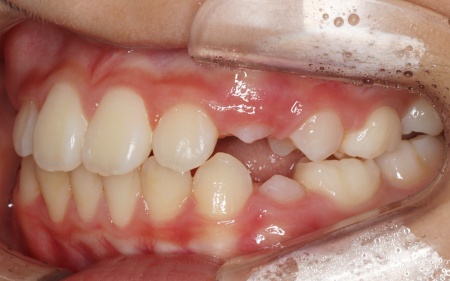

10歳女の子 顎の幅を広げる装置とマウスピース型の矯正装置で反対咬合を改善した症例

上顎の幅が整ったら、インビザラインファーストによる歯列の調整を開始します。

定期的に通院いただいてマウスピースの適合状態を確認し、計画通り歯が移動しているかを丁寧にチェックしました。

併せて、就寝時には前方牽引装置を使用していただいています。

後日、噛み合わせや歯並びが整ったことを確認し、矯正治療を終了しました。

現在は、3ヶ月に1回のペースで来院いただきながら経過観察を続け、永久歯の生え変わりに合わせて、必要に応じてリテーナー(保定装置)の調整も行っています。